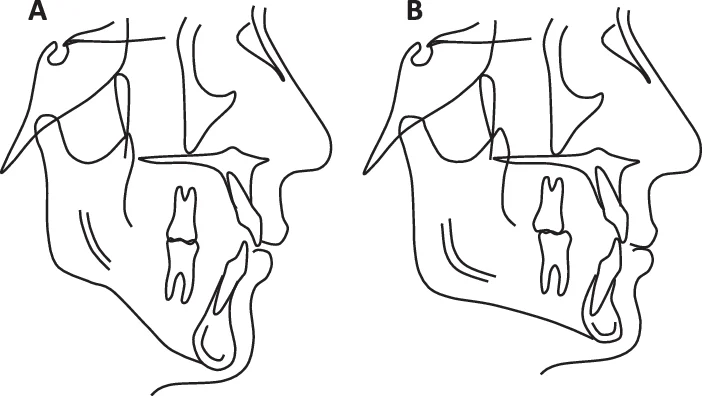

Cas Clinique 3 : Excès Vertical Antérieur Sévère — Traitement Chirurgical

Patient : Inès, 22 ans. Se plaint d’une « bouche qui ne se ferme pas » et d’un menton effacé. Complexée par son sourire.

Présentation : EVA sévère, face longue hyperdivergente, béance antérieure de 8 mm, inocclusion labiale au repos de 6 mm, menton rétrognathe. Angle mandibulaire ouvert. Croissance terminée (stade CS6). Ortho de décompensation préchirurgicale réalisée ailleurs (échec).

Problématique : Anomalie basale sévère dépassant les possibilités compensatrices orthodontiques. Seule la chirurgie orthognathique peut apporter une correction stable et esthétique.

Prise en charge :

- Bilan CBCT + simulation 3D de la chirurgie.

- Phase orthodontique préchirurgicale de 12 mois : alignement, nivellement, élimination des compensations.

- Chirurgie bimaxillaire : Le Fort I d’impaction maxillaire + ostéotomie de la branche montante d’Obwegeser-Dalpont + génioplastie d’avancement.

- Désinsertions musculaires complètes pour permettre le repositionnement libre du corps mandibulaire.

- Phase orthodontique post-chirurgicale de 6 mois : finitions occlusales.

Résultat attendu : Fermeture complète de la béance, amélioration majeure du profil, équilibre labial au repos. Stabilité excellente à 5 ans selon la littérature (Ricketts).

Point pédagogique : L’EVA sévère chez l’adulte est une indication chirurgicale. Toute tentative de compensation orthodontique prolongée retarde la solution stable et peut compromettre le projet esthétique. La collaboration orthodontiste-chirurgien dès le bilan initial est indispensable.